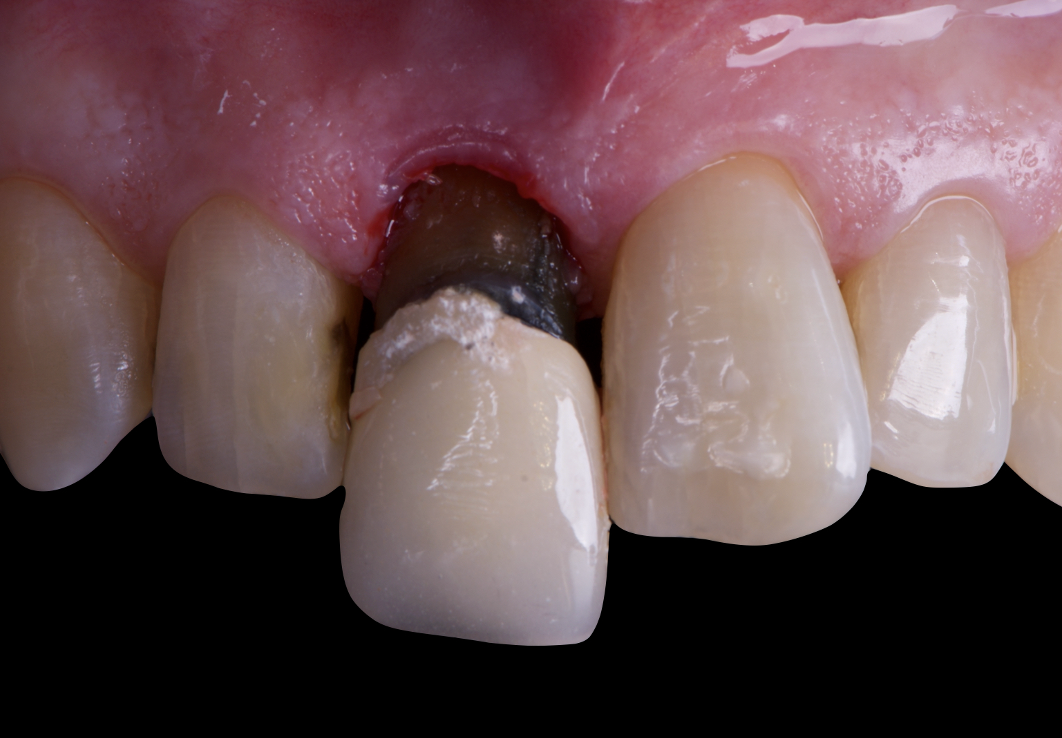

The surgical protocol began with the atraumatic extraction of tooth 1.1 to preserve as much of the alveolar socket as possible. Immediately following extraction, an N1 implant was placed into the socket using a guided surgical approach to ensure ideal three-dimensional positioning. The “one abutment one time” technique was applied to minimize soft tissue manipulation during the healing phase, which is particularly important in esthetic areas.

On the same day as the surgery, an immediate-load provisional crown was delivered. This restoration was fabricated in acrylic resin and screw-retained on the implant, following the “one abutment one time” principle. The provisional crown was carefully adjusted to avoid occlusal loading while supporting the peri-implant soft tissue architecture during the healing phase.

The provisional not only satisfied the patient’s functional and esthetic demands but also played a key role in shaping the emergence profile and conditioning the gingival margin. By providing a provisional solution immediately, the patient was able to leave the clinic with a natural-looking smile, avoiding any psychological or social impact associated with tooth loss in the anterior maxilla.